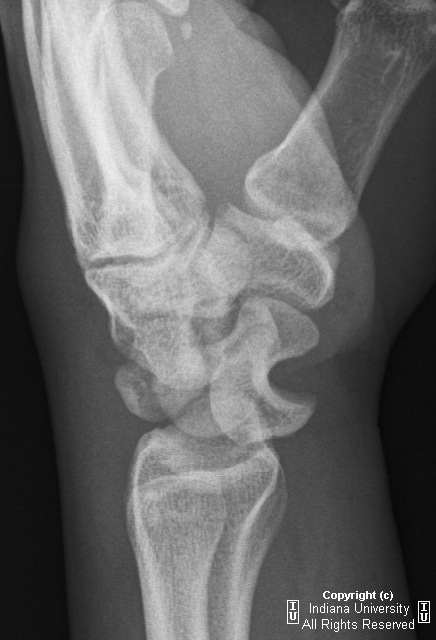

1).月骨脱位:正位片示月骨由四边形便成三角形或橘瓣状,并向尺侧移位。侧位月骨前移、旋转,窝状关节前空虚。

下面一例“月骨脱位病例”,请大家比较一下: